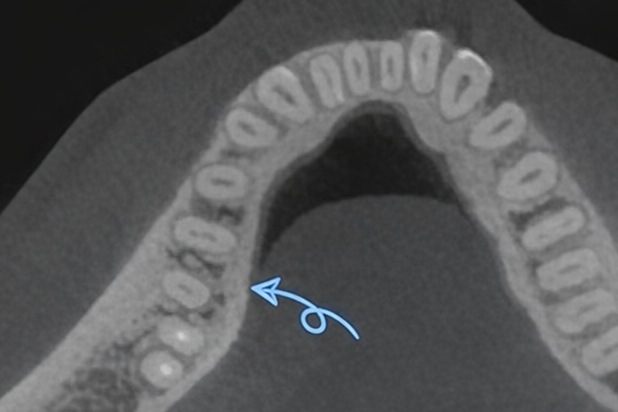

두 번째 형태 이상은 Radix Entomolaris입니다.

대개 아래쪽 큰 어금니에서 빈발하는데,

일반적으로 뿌리가 2~3개인 반면

Radix Entomolaris는 마곡동 치과

사진처럼 원심 설측에 치근이

하나 더 관찰되며 심하게 휘어 있고

신경관 입구가 멀리 떨어져 있습니다.

그래서 관찰조차 힘들고

치료 과정도 어렵죠.

입구를 찾았다고 하더라도 기구를 넣었을 때

파절되어 신경치료 과정이 다소

복잡해질 우려도 있습니다.

마곡동 치과 사진처럼 CT 자료에서 관찰되더라도

뿌리 자체가 심하게 만곡되어 있기 때문에

기구 파절이 흔히 생겨나기 때문이죠.

그래서 기구 파절 없이 안전하게 접근하여

내부 청결을 도모하기까지 복잡하여

다소 오랜 시간이 걸립니다.